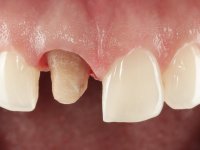

A pre-print was performed to make a crown in dual-cured resin. After a cross-section with a turbine, the infiltrated crown was removed with a microluxador. The dental stump was re-prepared to better define the shape and location of the cervical margin. It was necessary to place composite resin on the buccal surface of the provisional crown to improve its esthetics. The impression was made using a double-mix technique with two-viscosity, quick-setting silicones. In the laboratory, a crown with a ceramic-coated Zr infrastructure was made. After placing it in the mouth, we verified that the crown showed a greater translucency than the symmetrical one, not fulfilling our aesthetic goals. The ceramist had the opportunity to observe the situation in the clinic, collecting records for later rectification. The new crown was placed in the mouth and approved by the patient. The final cementation was done with resin-reinforced glass ionomer cement.